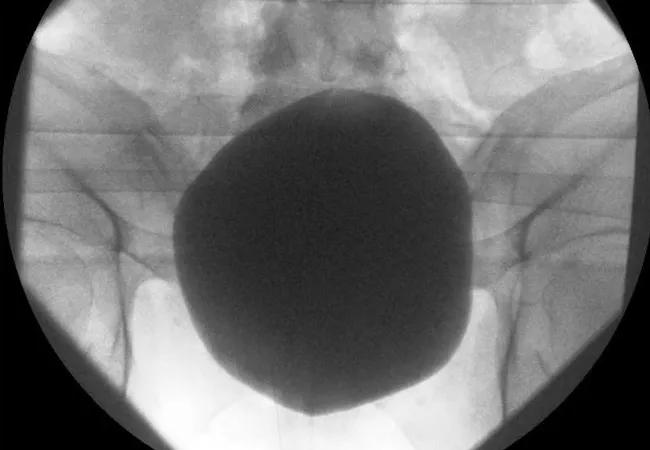

The study authors note that stroke patients often fulfill numerous criteria for placement of urinary catheters, such as bladder dysfunction and critical illness. They add that catheter-associated urinary tract infection is a serious problem and that reducing ‘catheter days’ is a worthy goal insofar as it targets unjustified catheter use. But the association of IUCs with inpatient morbidity is a complex issue, they contend, since failed IUC removal is itself associated with substantial morbidity, including increased risk of urinary retention and bladder overdistension (as shown in the image at the top of this post).